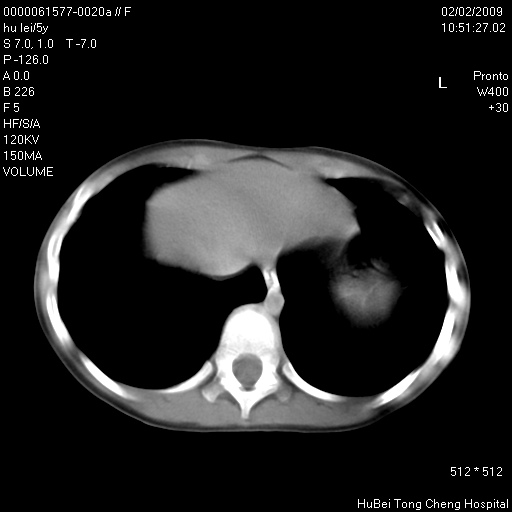

标题: PED1732:M5Y,右肺囊性占位!

患者:男,5。无明显不适,拍胸片考虑右肺囊肿。

行ct扫描,图象如下:

病灶与前胸壁和右上纵隔、叶间裂界限不清,病灶前缘及内侧缘看不到正常的肺组织,不能排除包裹性积液。